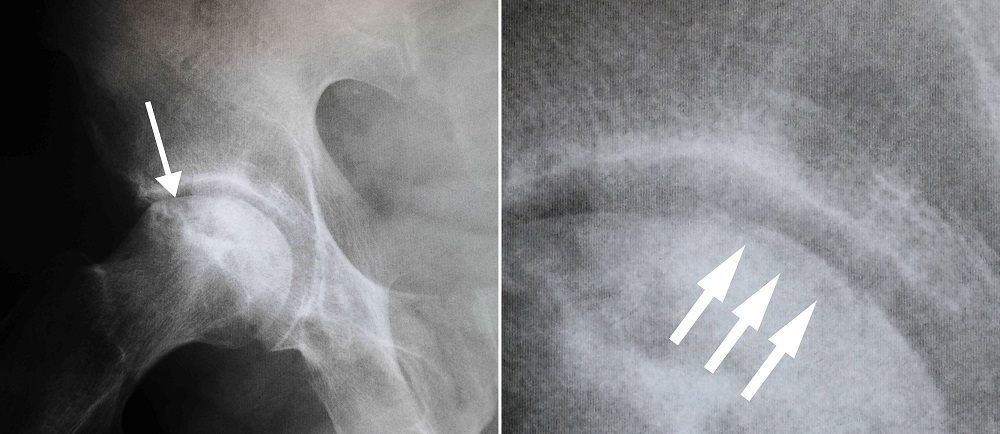

Диагностика ТБС рентгеном и асептический некроз: особенности лечения

Раздел: Снимки-откровения